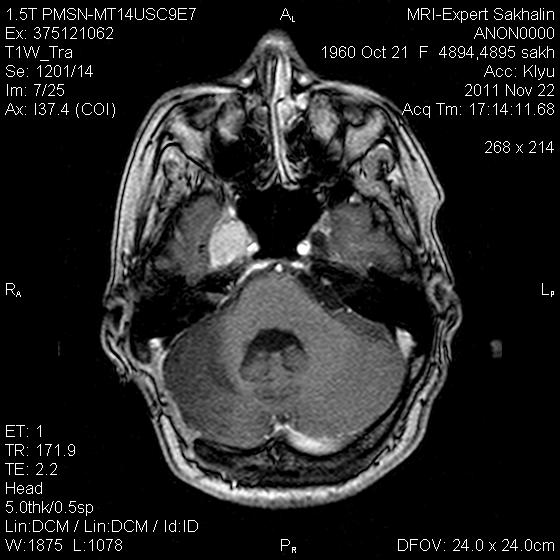

Петро-кливальная менингиома-рецидив?

Женщина по направлению нейрохирурга.В мае 2011  года оперирована по поводу петро-кливальной менингиомы ( где конкретно-слева или справа-история умалчивает, предыдущие исследования и описания не представила).Кроме менингиомы  нашла еще несколько изменений в головном мозге.Хочу послушать мнение уважаемых коллег и сравнить со своими умозаключениями.Это для самоконтроля-честное слово!

Не специалист в МРТ. Образование в правой височной доле (?), сбоку от турецкого седла. Изменения сигнала в правом полушарии мозжечка, расширение 4-го желудочка.

Судя по глиозным изменениям справа, дефекту затылочной кости кости - было справа и оперировали через поперечный синус. Стало быть - рецидив.

Состояние после провденного оперативного лечения в ЗЧЯ (кистозно-глиозные изменения в правом полушарии мозжечка, послеоперационный костный дефект затылочной кости справа). Объемное образование медиобазальных отделов правой височной области (параселлярно справа). Хорошо копит контраст. Возможно - рецидив, возможно остаточный фрагмент или продолженный рост... Надо знать что было до операции... Не вижу "кливального" компонента... Не исключено распространение в проекцию основной пазухи (по моему как минимум деформирована ее стенка).

Еще не нравится что "копит" намет парасагитально справа, но толком не рассмотреть...